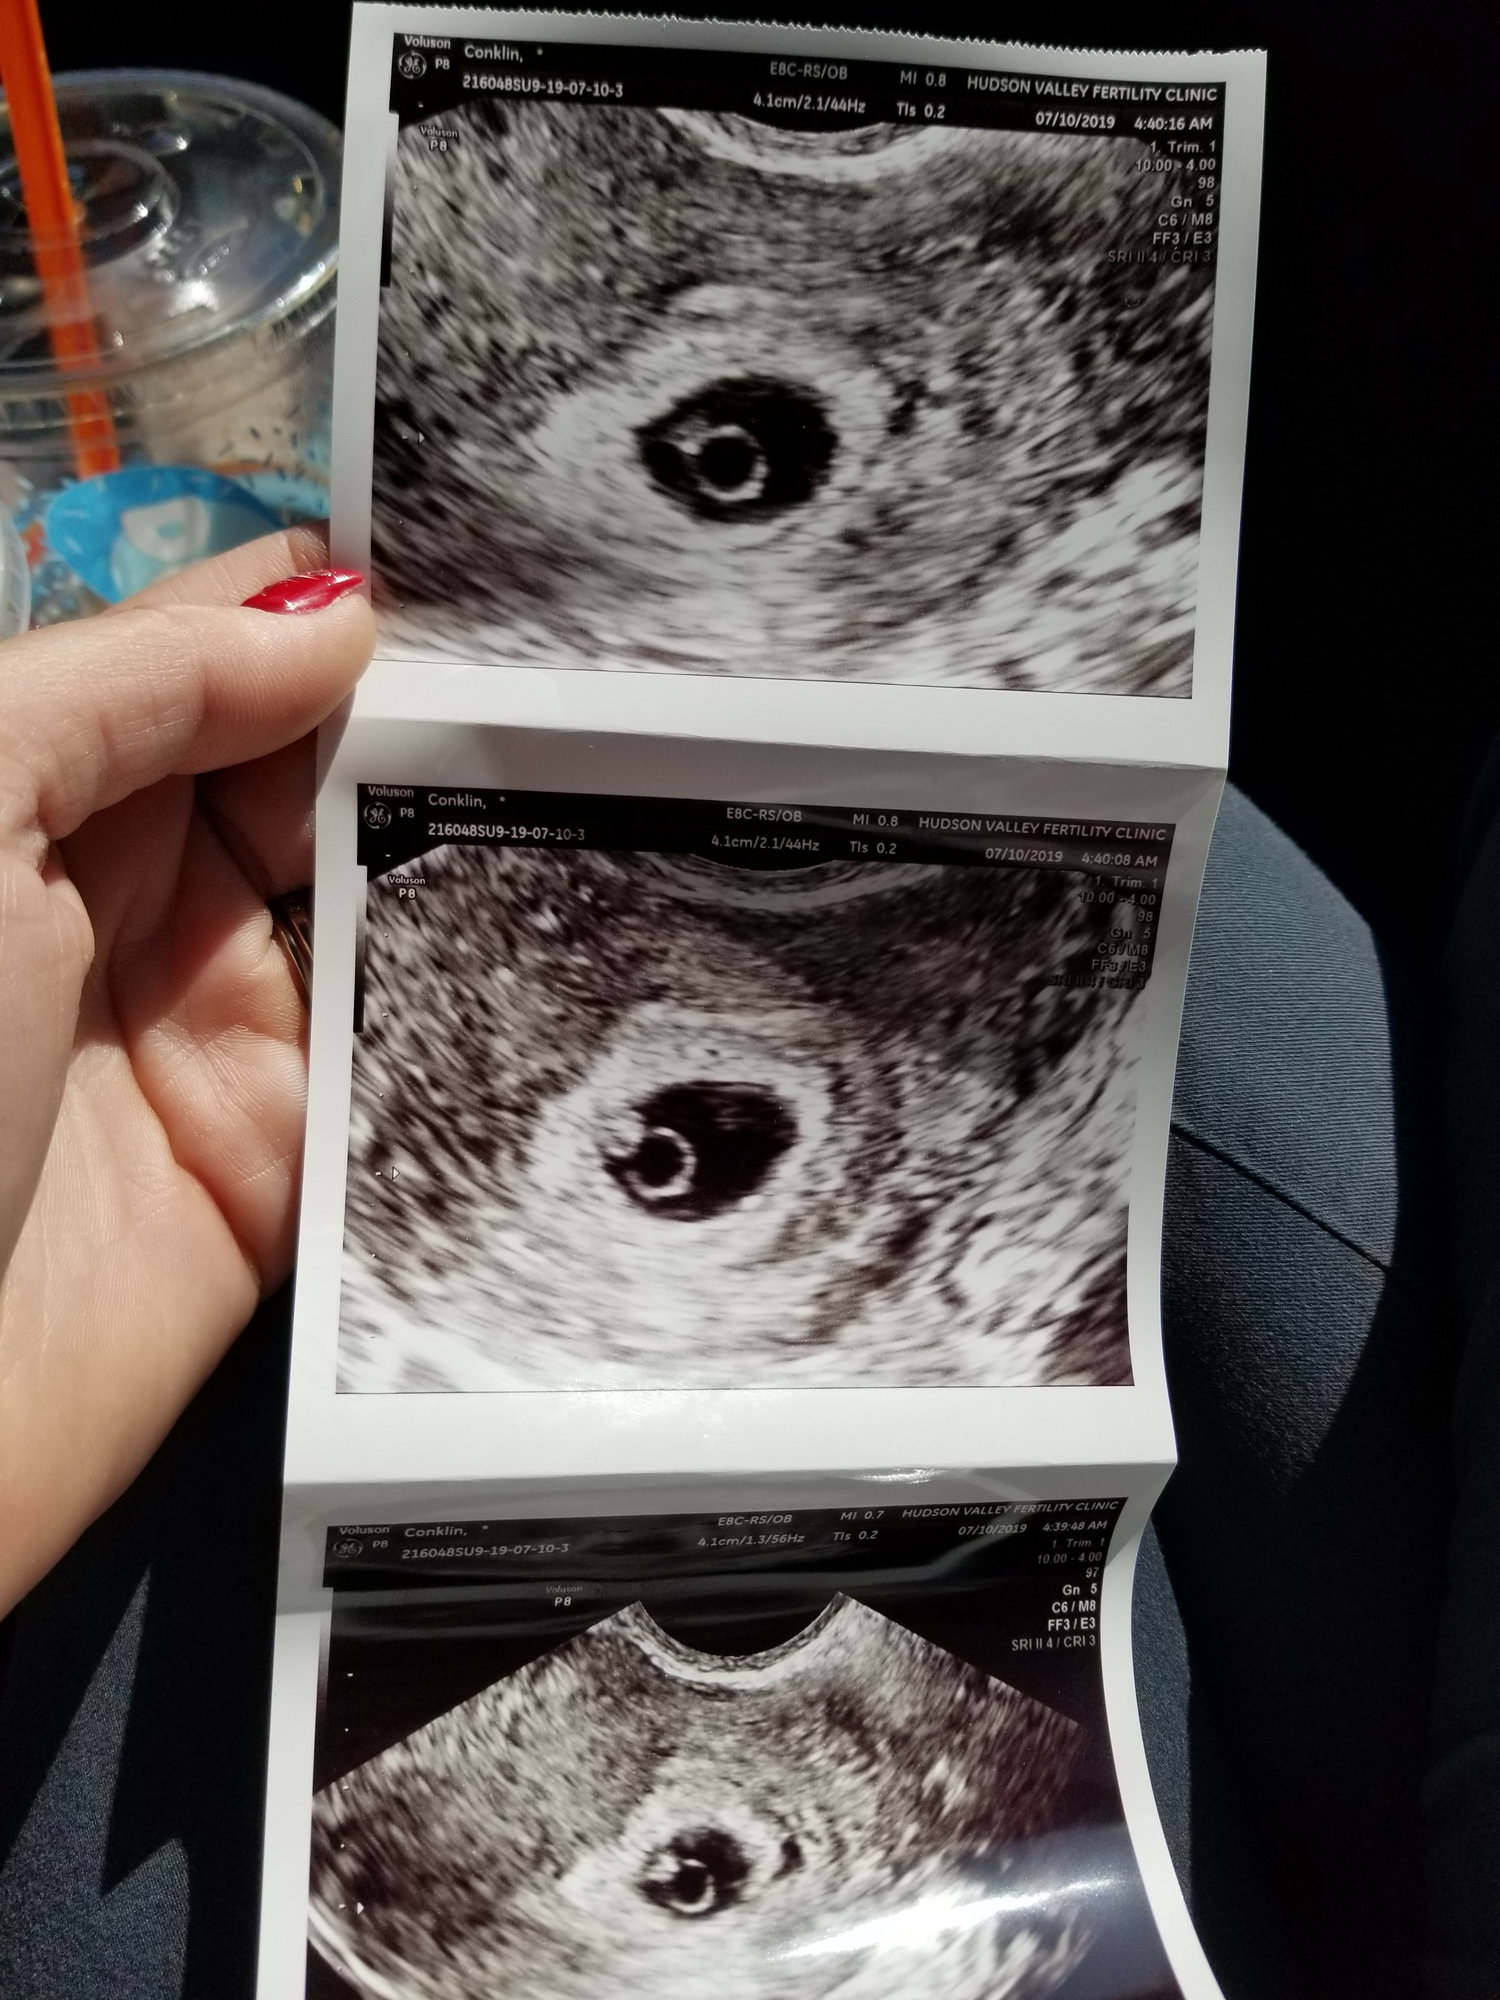

@aconklin214 EDD 3/3

• How far along/EDD? 6w5d 2/25

• How are you feeling this week? Exhausted. Feel like I pee every half hour lol. Super anxious about my first scan tomorrow

• Any upcoming appointments? 1st scan tomorrow 7/9

@aconklin214 congrats on scan.  That's fabulous news.

@acconklin214 - that’s great that your US went well! It must be such a relief!

• Thank you all so much for your support!  the US went perfect today!!!!  We got to see our little baby and the HB was 137 which they said is exactly where it needs to be.  There is a huge sense of relief but also fear as we graduated from our RE.  Now we start a long wait because my OB appointment isn't until 08/08 which I think is a really long time.  I'll be 11 weeks then and I might call and clarify because that seems like too long of a wait but maybe I'm just impatient.